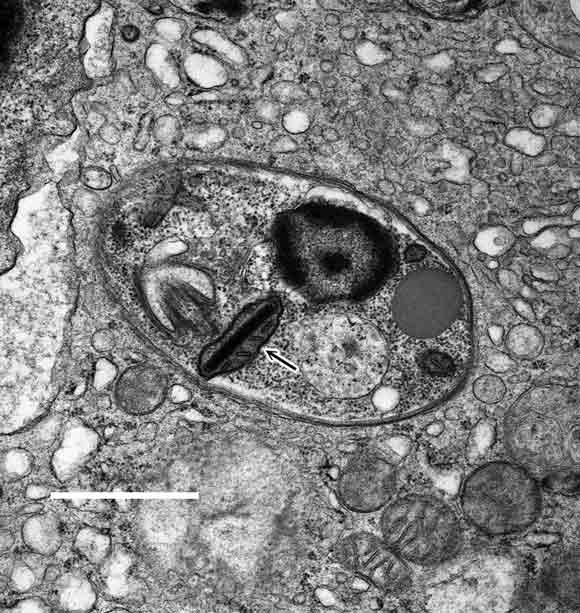

Transmission electron micrograph of bone marrow, showing an amastigote with a kinetoplast characteristic of Leishmania spp. (arrow). (Scale bar = 1 μm.)